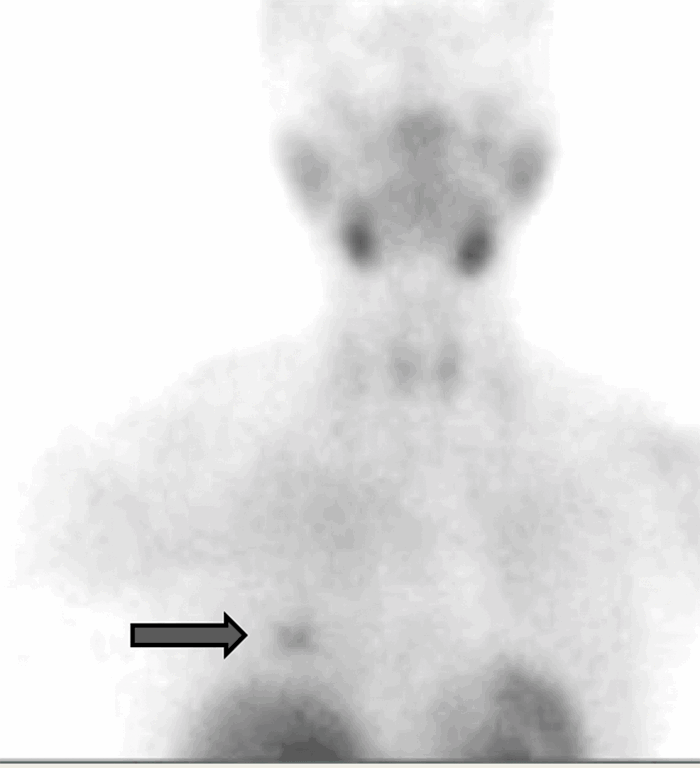

A 59-year-old female presented initially with vague symptomatology of hyperparathyroidism. She had a history of type 2 diabetes and hypothyroidism, and her medical workup confirmed a biochemical diagnosis of mild primary hyperparathyroidism. She was referred for surgical evaluation. Localization studies to identify her hyperfunctioning parathyroid included neck ultrasound and sestamibi scan with SPECT CT. Ultrasound imaging was nonlocalizing for a parathyroid lesion; however, sestamibi scan revealed suspicious tracer uptake in the right breast (Figure 1).

Figure 1.Sestamibi scan: Sestamibi imaging demonstrating uptake in the right breast.